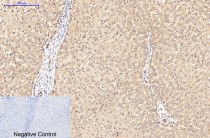

ARG66176 anti-eIF4A1 antibody IHC-P image

Immunohistochemistry: Paraffin-embedded Rat spinal-cord tissue stained with ARG66176 anti-eIF4A1 antibody at 1:200 dilution (4°C, overnight). Antigen Retrieval: Boil tissue section in Sodium citrate buffer (pH 6.0) for 20 min.

Negative control was used by secondary antibody only.